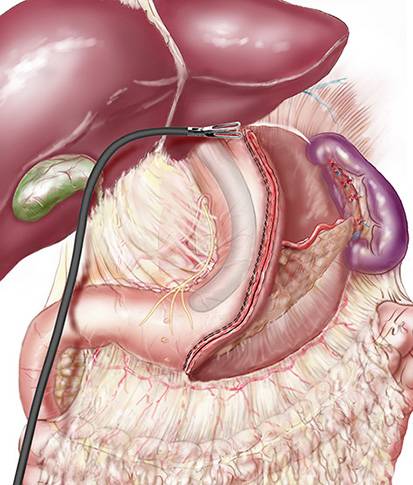

Traitement chirurgical des hernies internes après bypass en Y: une Expertise du groupe MUST à Paris

La hernie interne (HI) fait partie des complications chroniques les plus fréquentes après bypass gastrique en Y (BPGY). L’incidence de cette complication dép...